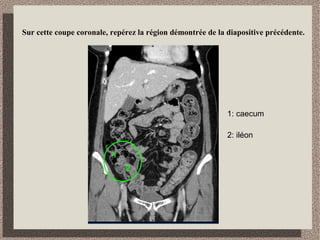

Sur cette coupe coronale, repérez la région démontrée de la diapositive précédente.

1: caecum

2: iléon